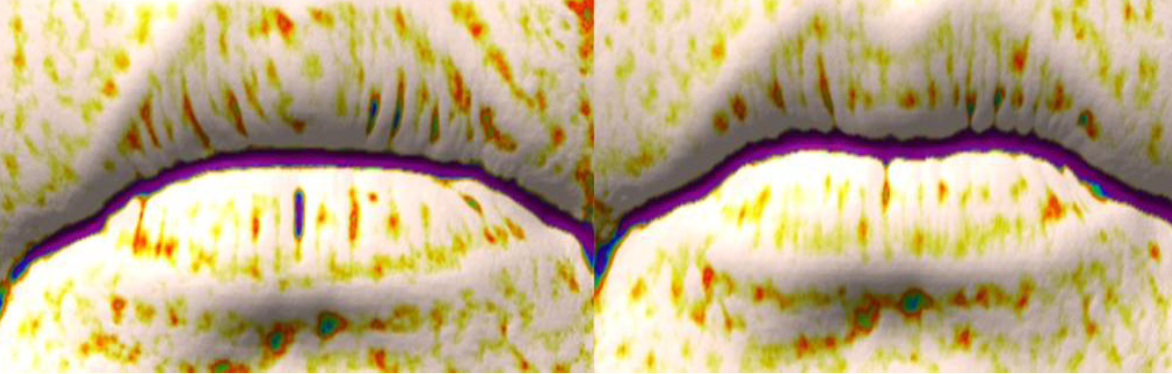

目尻シワの深さ・唇シワの軽減・肌のハリ・明るさ・化粧ノリの改善など、多方面で有意な改善が確認されました。

肌のキメ 毛穴 唇シワ

客観的指標の変化 1 客観的指標の変化 2

「レチニアミド発酵液」 を4週間朝夜2回塗布することにより、スキンケアをしない無塗布と比べ、目尻シワ(抗シワ評価はクリアーした)・肌の保湿・肌のハリ・目元のたるみ・肌の明るさ・肌のキメ・毛穴・唇のシワの改善効果が確認出来た。試験期間中に肌の異常を訴える者はおらず、経過観察期間2週間後においても肌に異常を訴える者はいなかったので安全性に関して問題ないことが確認された。